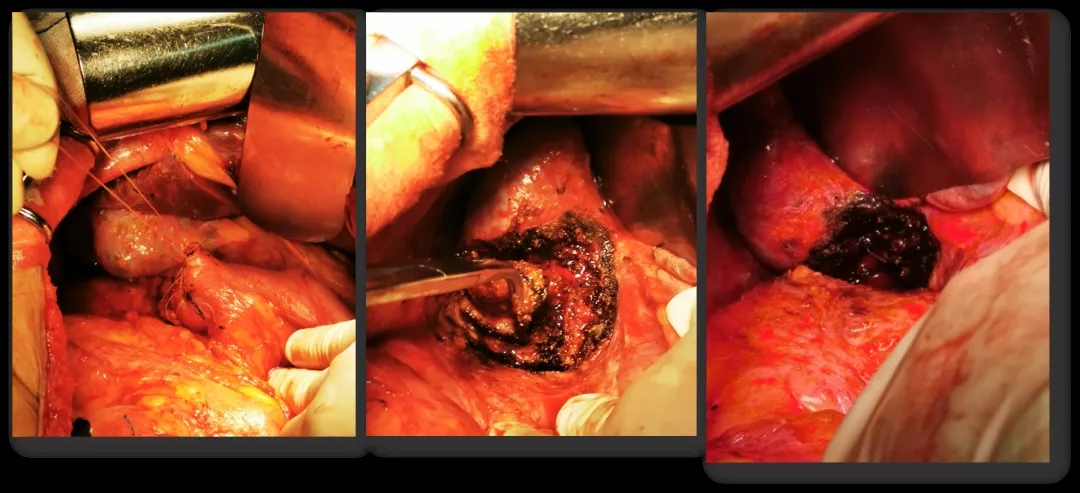

2016.10.26行三次减瘤术(乙状结肠部分切除侧侧吻合+腹盆腔减瘤+腹膜后淋巴结切除),术后无肉眼残留。

术中所见

病理诊断